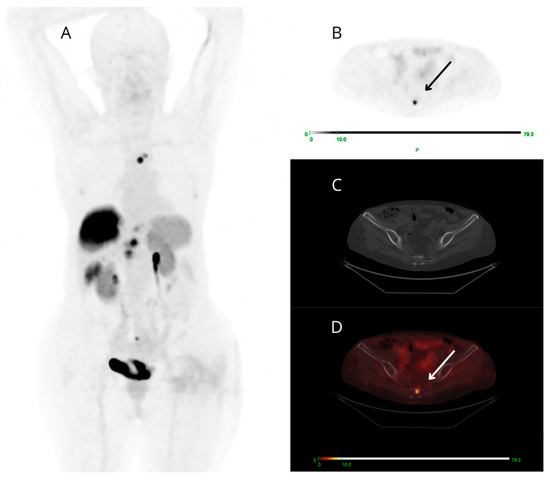

Among the 13 PET-positive targeted small findings (all true positive), 6/13 cases presented ceCT-negative small lesions (at bone level in 4/6 patients and node level in 2/6 cases) (Figure 4), 2/13 showed both small-sized PET-positive lesions (false negative on ceCT) and additional small-sized lesions reported as indeterminate on ceCT that were not detectable on PET/CT. There was also a small group of only 5/13 patients presenting both concordant and discordant PET-positive findings: each case presented a target PET-positive small finding confirmed by ceCT (concordant true positive) and a small finding clearly avid on PET images (2 pancreatic, 2 nodal and 1 at soft tissue level), known as malignant at ceCT only after expert radiological revision, aware of the PET result.

Figure 4.

Maximum intensity projection (MIP) (A), PET (B), CT (C), and fused PET/CT (D) transaxial images of a patient studied for restaging of metastatic G3 NET, likely of pancreatic origin. [68Ga]Ga-DOTANOC PET shows high and focal uptake at the coccyx (arrows). The uptake area does not correspond to clear morphologic alterations on low-dose CT.